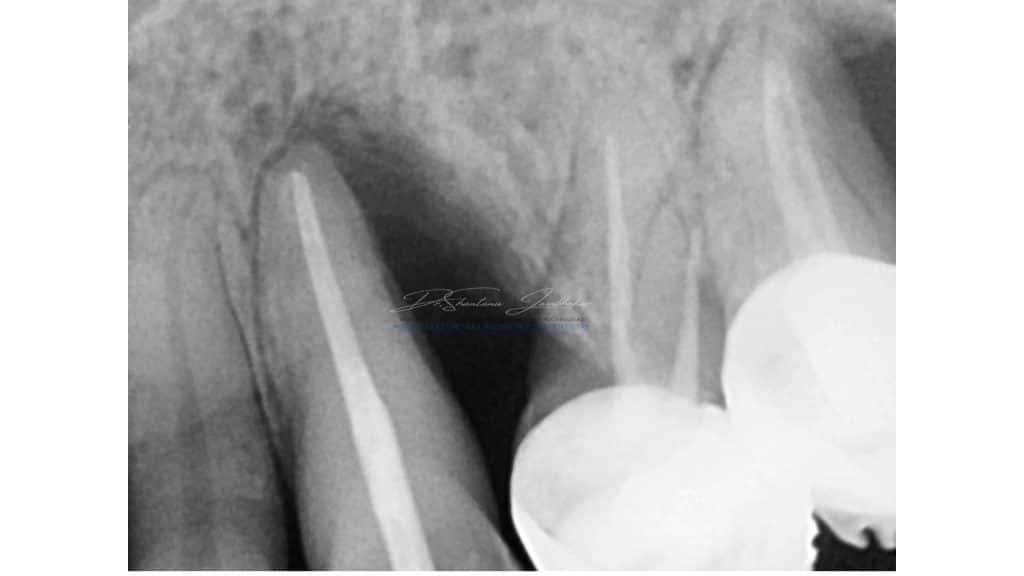

Radiographic examination revealed radiolucent lesion with 23,25 and reduced residual ridge dimensions with sites 26 & 27. Cone beam CT (CBCT) evaluation was performed for available quantity & quality of bone at the proposed implant sites using CS 3D Software.

Pre-Treatment IOPA showing the periodontal defect